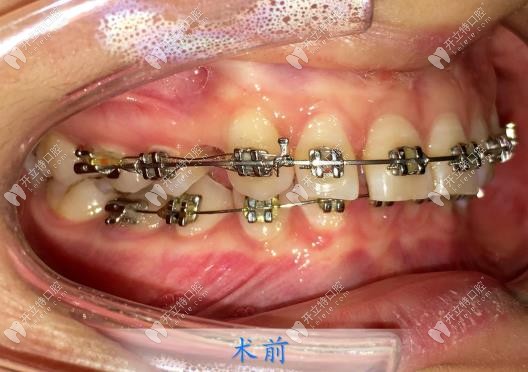

我也是比較糾結(jié)選哪款牙套,因?yàn)橐彩莿偣ぷ鳑]多久,經(jīng)濟(jì)有點(diǎn)拮據(jù),楊醫(yī)生就推薦我做金屬的,上頜牙可以用方絲弓矯正,力道會充足一些,下牙需要做一點(diǎn)小調(diào)整就行,可以用細(xì)弓絲。矯正的還快,效果也更穩(wěn)。

說真的,我面診了這么多家牙科,只有楊醫(yī)生是站在我角度上去為我想的,當(dāng)下就決定在這矯正了!不過因?yàn)槲已例X有點(diǎn)前突,需要先拔牙,然后才能內(nèi)收齙牙,敲定方案和價格后,我當(dāng)天就拔了一顆牙,不得不說,楊醫(yī)生手法很嫻熟,拔牙并不疼!

然后過了差不多半個月后,我就到院內(nèi)戴牙套了,楊醫(yī)生很細(xì)心,每一個托槽粘的都很認(rèn)真,他說這樣也是能防止后期托槽脫落帶來不必要的麻煩,我就更認(rèn)可楊醫(yī)生了!